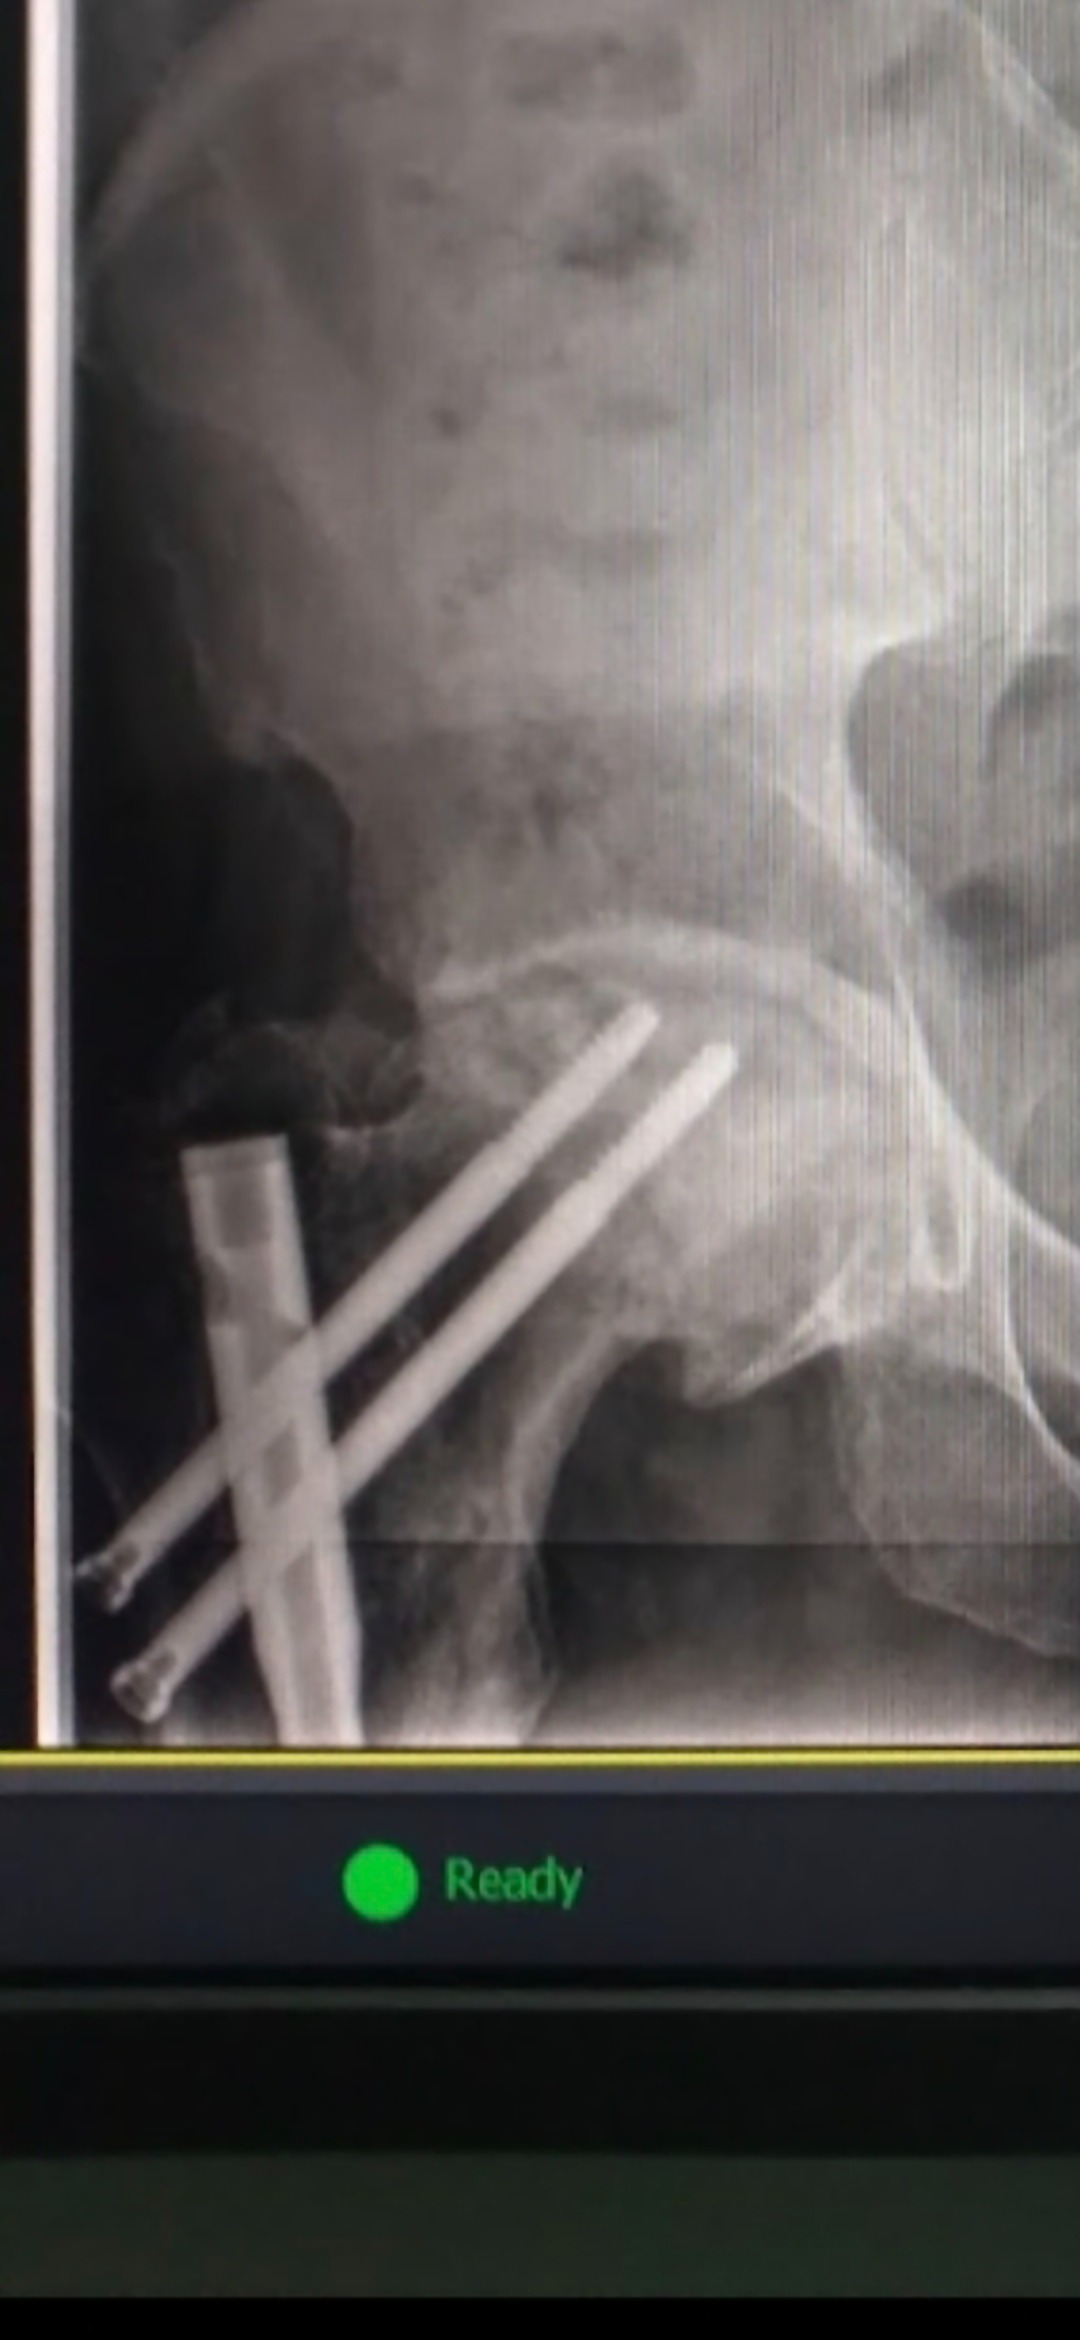

Our dear friend Oliver is facing a major surgery to replace his hip. Anyone who knows Oliver knows just how much he gives to our recovery community — offering support, encouragement, and a listening ear to so many of us on our journeys. Now, it’s our turn to show up for him.

Oliver has already been unable to work since March due to his condition. This has made his financial need even greater, but those who know him also know it’s worth helping him gain the quality of life he deserves — especially after all he has done for others.